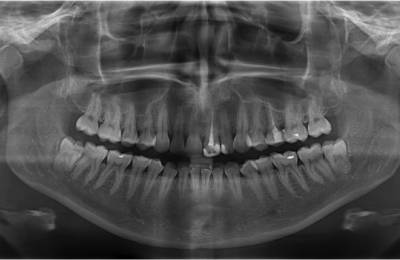

• панорамное костно-челюстное рентгенологическое сканированиепровести конусно-лучевую томограмму;

• сделать панорамное костно-челюстное рентгенологическое сканирование;

• выполнить точечный рентгенологический снимок зуба и прочее.